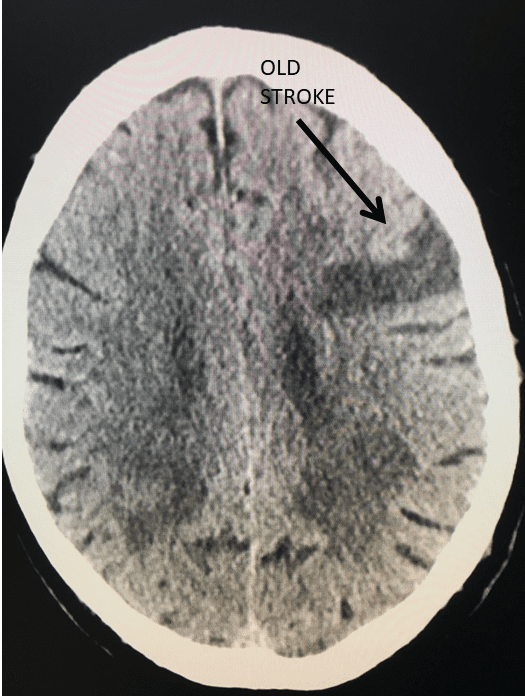

Endovascular:

Carotid Cavernous Fistula (CCF)

Author: Jonathan L. Brisman M.D., F.A.C.S., Read More!